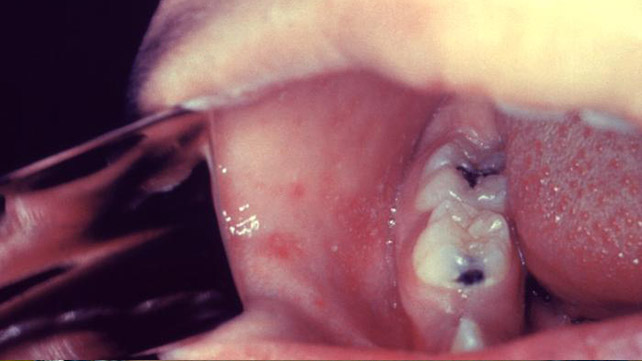

科普利克的景点

在您第一次注意到麻疹症状之后的两三天,您可能会看到嘴里的小小的斑点,遍布脸颊。 这些斑点通常是红色和蓝白色的中心。 他们被称为Koplik的斑点,以儿科医生Henry Koplik的名字命名,他在1896年首先描述了麻疹的早期症状。当其他麻疹症状消失时,Koplik斑点应该消失。